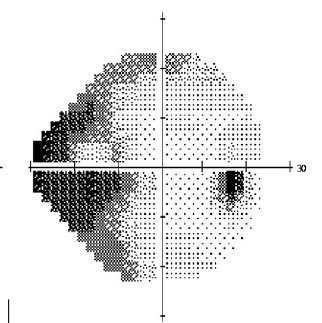

灰度图

4.jpg

图 4 灰度图

灰度图具有直观易懂、一目了然的特点,对于初学者而言,拿到一张视野报告时最容易注意到的就是灰度图了。但需要注意的是,灰度图是直接把测得的视敏度用不同的色阶表示,只是一个粗略的定性表达。另外,实际上,实测的视敏度受年龄、屈光介质等因素影响变化很大,因此,绝对不能直接用灰度图得出视野缺损状况的评估结论!

按这个顺序读完一遍,相信你已经对病人的视野情况了然于心。比如本文中举例的这张报告,就是一个典型的颞侧视野缺损。实际上,这位患者的颞侧视野缺损是双眼同时存在的,由枕叶梗死导致,视野缺损对明确病变定位起到了重要辅助作用。